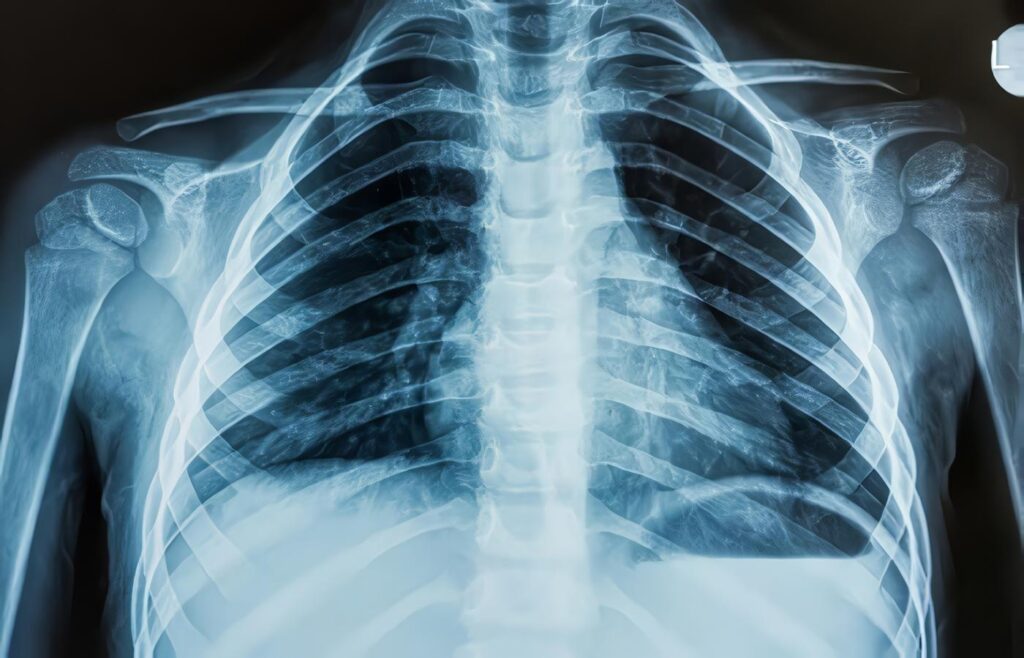

Desempeño Diagnóstico de la Radiografía de Tórax Digital en Decúbito para la Detección de Derrame Pleural

María Antonieta Londoño1, Luis Felipe Uriza2 Fabián Armando Gil Laverde3, Lina Marcela Salazar4 Resumen Objetivo: Calcular las características operativas...

Detección de Derrame Pleural, Análisis Estadístico

El análisis y comparación de las pruebas diagnósticas se realizó mediante la Curva de rendimiento diagnóstico (COR, del inglés ROC:...

Detección de Derrame Pleural, Discusión

En estudios realizados con el fin de detectar derrame pleural en radiografías, Woodring reportó una precisión de 0,95 al evaluar...